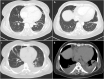

Presentation of case: A 47-year-old female presented with bilateral pulmonary infiltrates and non-specific symptoms as fever, chest pain and dyspnoea on exertion. She was treated with antibiotics for suspected lung infection but deteriorated developing rapid recurrent pleural effusion. Her transthoracic- and transoesophageal-echocardiography as well as the thoracentesis and endobronchial ultrasound findings were normal. A minimally invasive pulmonary wedge resection, partial pleurectomy and pericardial fenestration was performed. The pathologic interpretation of these specimen was very difficult and a correct diagnosis could be made only by the second reference pathologist. While awaiting reference histology report she was administered high-flow oxygen therapy for hypoxia, antibiotics, catecholamines and corticosteroids. The patient deteriorated very rapidly and died in the ICU.